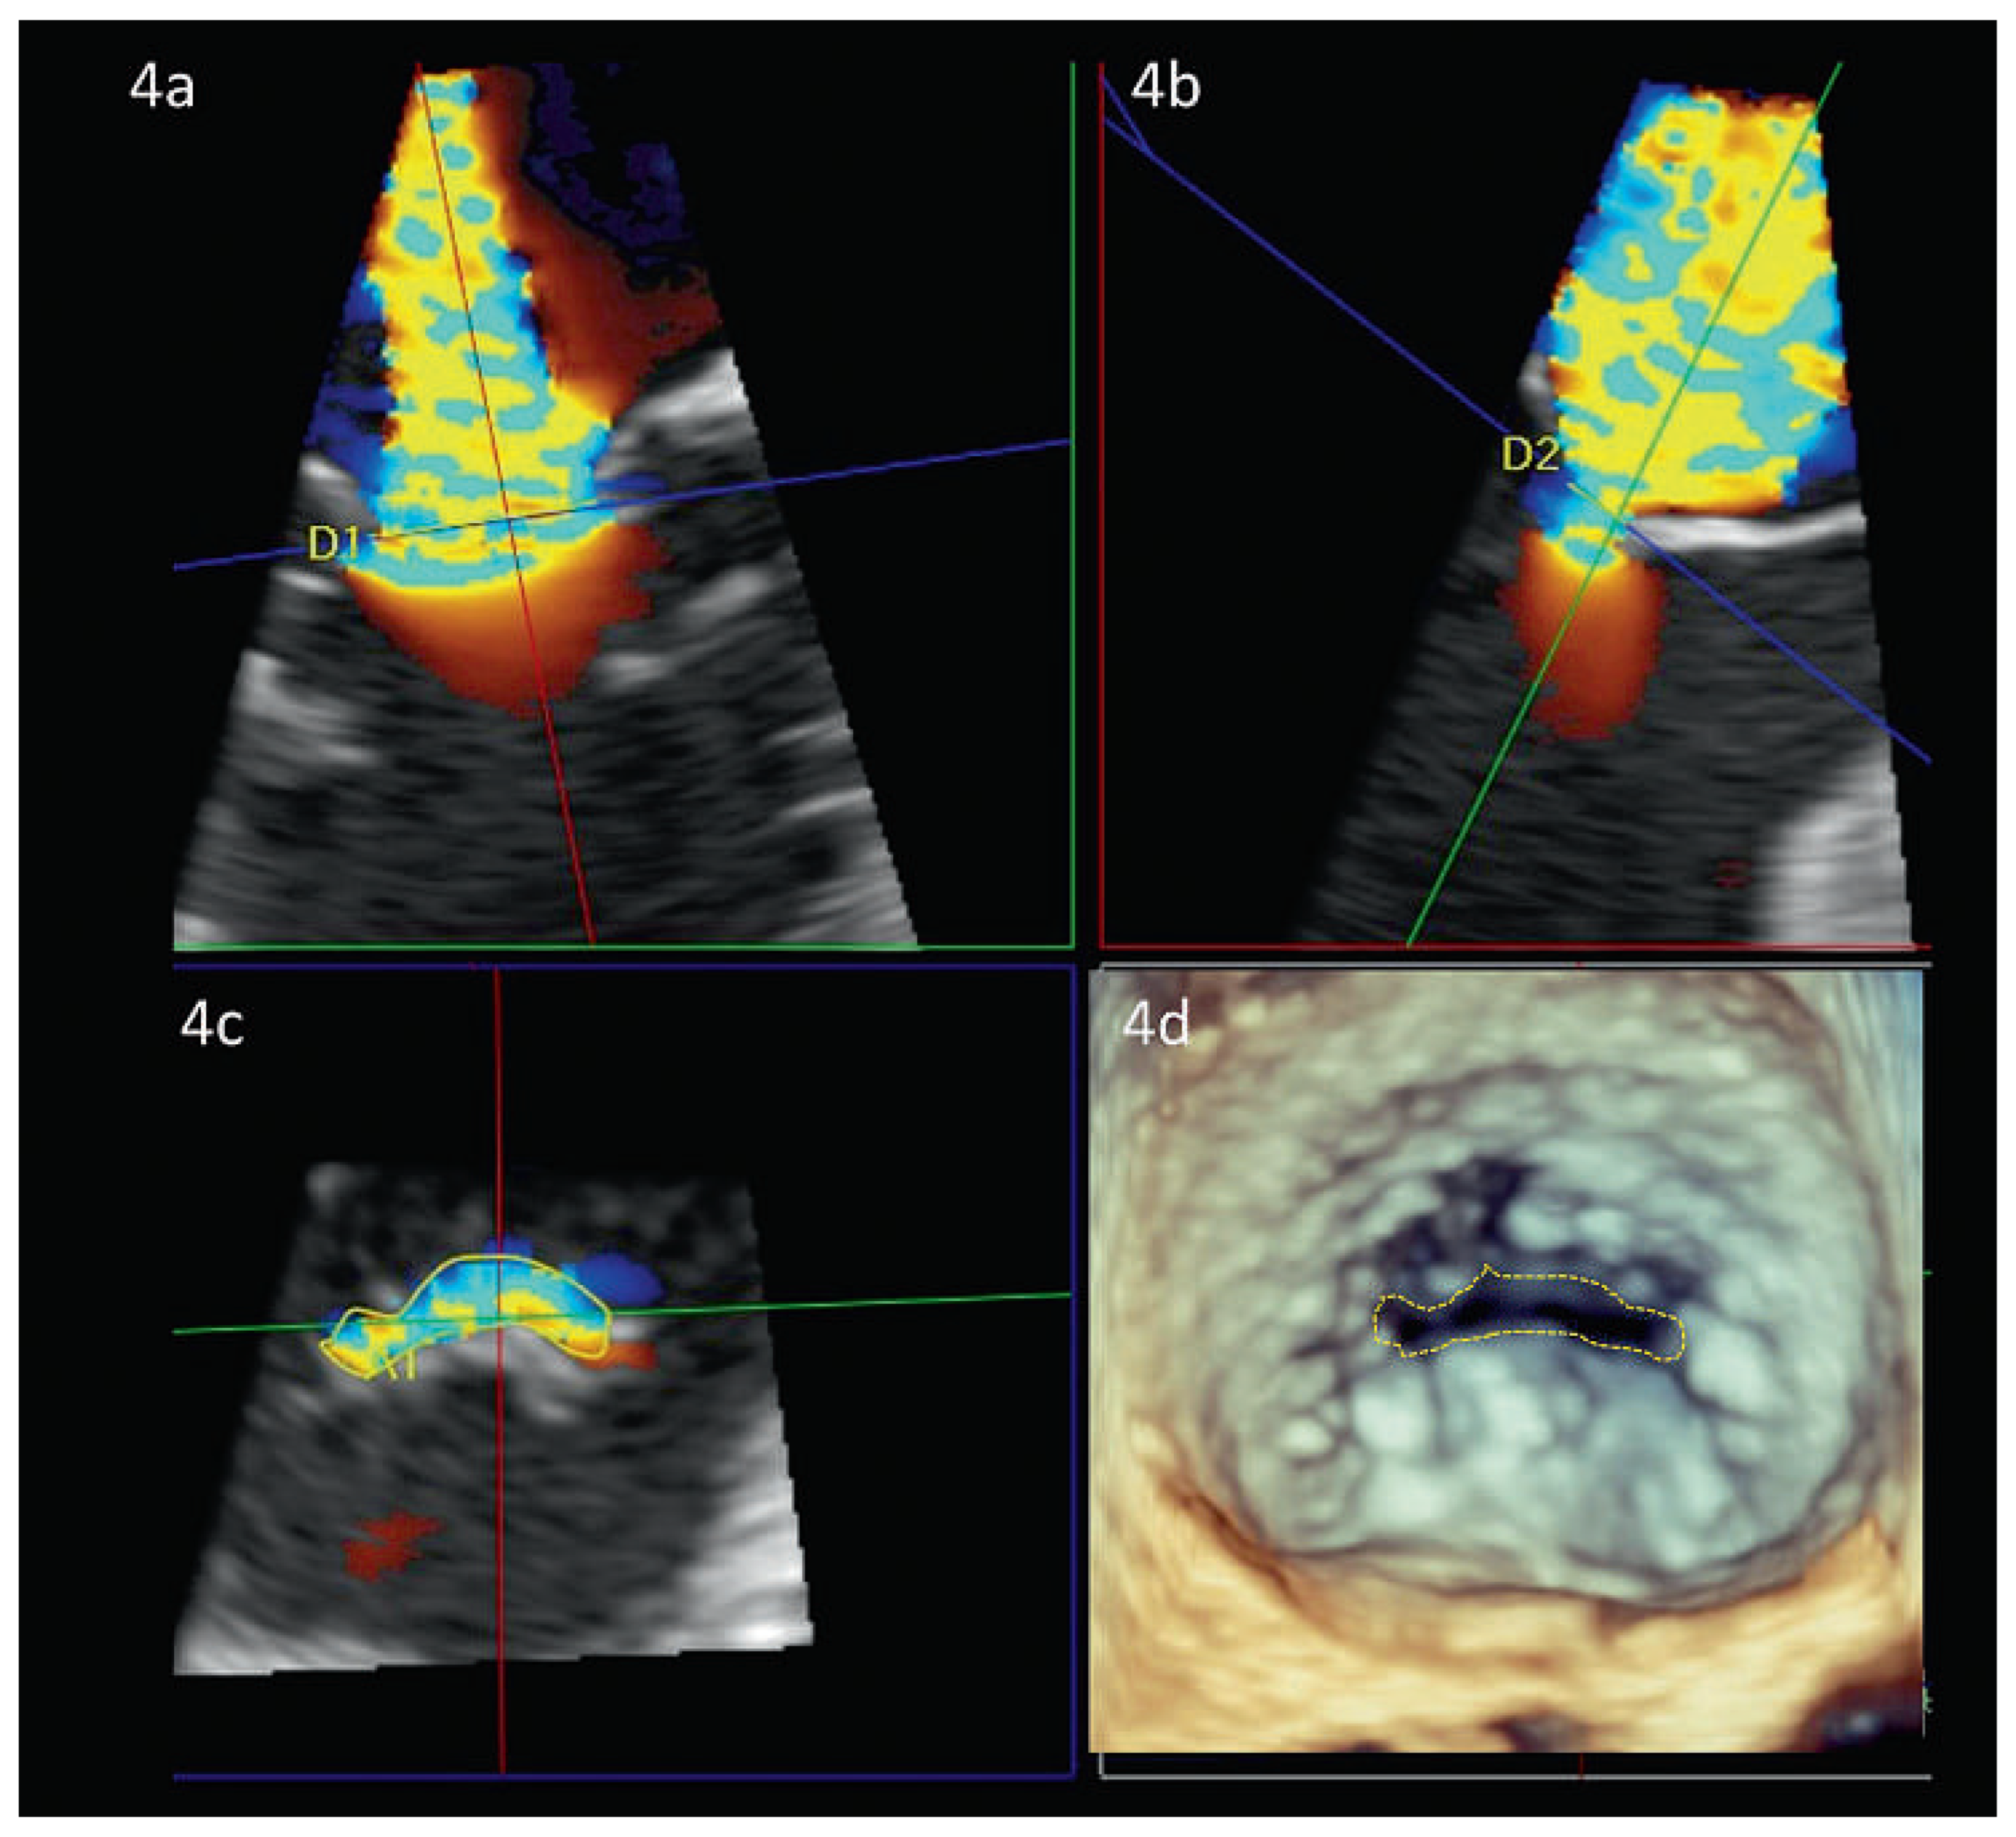

Abbildung 4. VC-Area und anatomische Regurgitationsfläche (ROA) bei funktioneller Mitralinsuffizienz. Darstellung der Vena contracta area (VCA) mittels 3D Datensatz (hier 3D TEE). Die grüne (Abb. 4a) und rote Ebene (Abb. 4b) stehen senkrecht zueinander und werden so in den 3D-Datensatz gelegt, dass sie die maximale Regurgitation zeigen. In beiden Abbildungen wird die blaue Ebene nun auf Höhe der Vena contracta gelegt (blaue Linien). In Abb. 4c kann nun die VCA gemessen werden. Abb. 4d zeigt zum Vergleich die anatomische Regurgitationsfläche (AROA) in der 3D-Echokardiographie.

Als Vena Contracta (VC) wird der Bereich eines Jets bezeichnet, der die geringste Fläche und die höchste Geschwindigkeit aufweist (Abbildung 4). Typischerweise liegt sie direkt hinter der Regurgitationsöffnungsfläche. In der 2D-Echokardiographie wird die VC mittels Farb-Doppler Untersuchung in der parasternalen Längsachse (und nicht im Vieroder Zweikammerschnitt!) gemessen [18]. Falls die effektive Regurgitationsöffnungsfläche (EROA) kreisförmig ist, kann sie mittels VC annähernd ermittelt werden (π* [VC/2]2). Meist ist die EROA allerdings ellipsoid bzw. halbmondförmig (bei funktioneller Mitralinsuffizienz) oder von irregulärer Form (bei multiplem Prolaps).

In den letzten Jahren sind verschiedene dreidimensionale transthorakale und transesophageale Methoden zur Quantifizierung der Mitralinsuffizienz entwickelt worden: Die 3D-VC-Area (Abbildung 4d) [19], das 3D-Regurgitationsvolumen [20], die 3D-Planimetrierung der anatomischen ROA (AROA, Abbildung 5) [21] sowie die 3D-Color-DopplerEchokardiographie mit Flussvolu-metrie (s. Abbildung 6) oder mit 3D PISA-Methode [22]. Alle Methoden überzeugen gegenüber den 2D-Berechnungen, weil sie nicht mehr auf geometrischen Annahmen basieren und damit einen gewichtigen Fehler ausschalten. Prinzipiell ermöglichen sie auch die Quantifizierung von komplexen und multiplen Regurgitationsjets. Die reduzierte zeitliche und räumliche Auflösung sowie die teilweise sehr zeitaufwändigen Techniken limitieren jedoch deren breite Anwendung im Alltag. Speziell die 3D-PISA-Methode mittels der neu entwickelten single-beat real-time 3D-Color-Doppler-Technik ist eine vielversprechende Methode bei Trikuspidal- [23] und Mitralinsuffizienz [24]. Dies insbesondere daher, weil erstmals die verschiedenen Beschleunigungsareale, welche über die Zeit entstehen, integriert werden und damit der Zeitpunkt der Messung nicht mehr ins Gewicht fällt. Bisher sind die Arbeitsschritte dieser Methode aber noch nicht vollautomatisiert. Es müssen immer noch betrachterabhängige Korrekturen gemacht werden, welche die Reproduzierbarkeit auch dieser Methode limitieren.